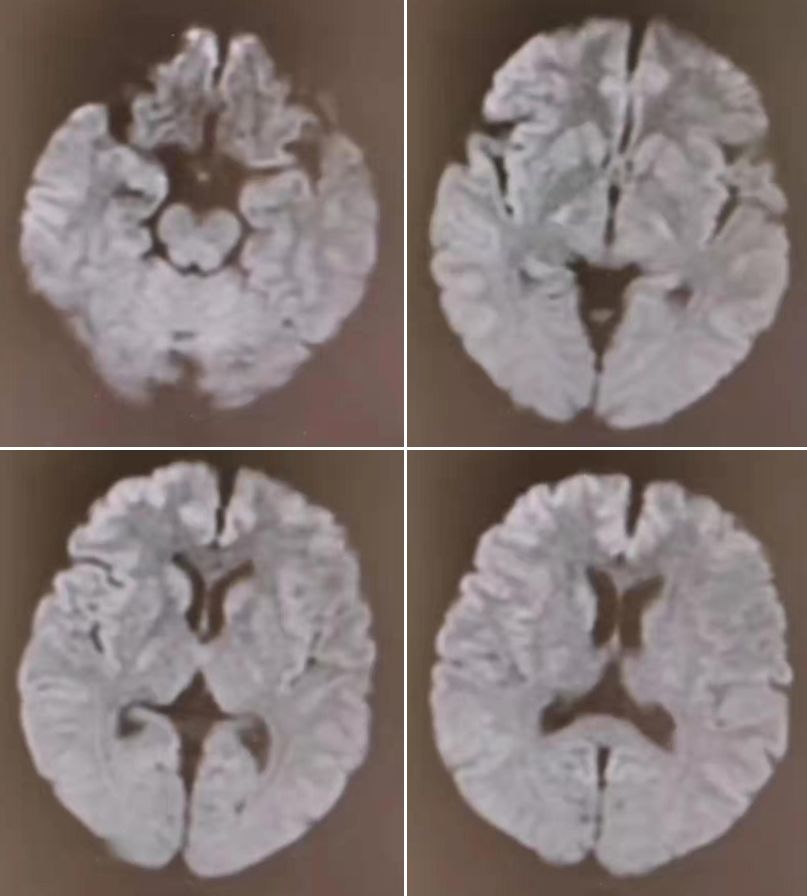

10月11日核磁如下:

3天后复查:

核磁只给了DWI序列,复查对比可见,双侧颞叶、岛叶、额叶皮层广泛、对称高信号,所谓皮层“花边征”。

诊断: 高氨血症。

1. 对称性双侧皮质受损,弥散受限、T2及FLAIR信号增高,特别是在岛叶和扣带回皮质,而在中央沟旁顶叶皮层、枕叶中央皮质及基底节区往往不受累。

2. 严重的损伤往往可影响上述相对不受累的区域,甚至基底节区、丘脑、皮质下白质及脑干也会受累。

3. 影像学特点及临床表现在治疗后往往是可逆的,根据疾病的严重性及高氨血症的持续时间而有所不同。

有群友把皮层花边征的鉴别诊断总结了一句顺口溜:“低糖高氨上吊死,疯牛脑炎偏头痛”。低糖:低血糖脑病;高氨:高氨血症;上吊:自缢;死:猝死、心跳骤停、缺血缺氧性脑病;疯牛:克雅氏病;脑炎:自身免疫性脑炎。再加上癫痫持续状态及MELAS,涵盖了绝大多数DWI皮层“花边征”高信号鉴别。